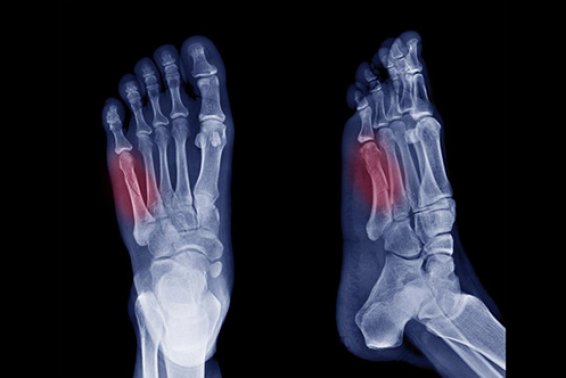

Increasing numbers of stress fractures

During the last few months I have seen an increasingly high number of foot stress fractures in my clinics. My assumption ...

The 5 most common fractures around the foot and ankle

Fractures, or broken bones, are common and temporary debilitating injuries. However, with appropriate treatment, patients can often regain their previous level ...